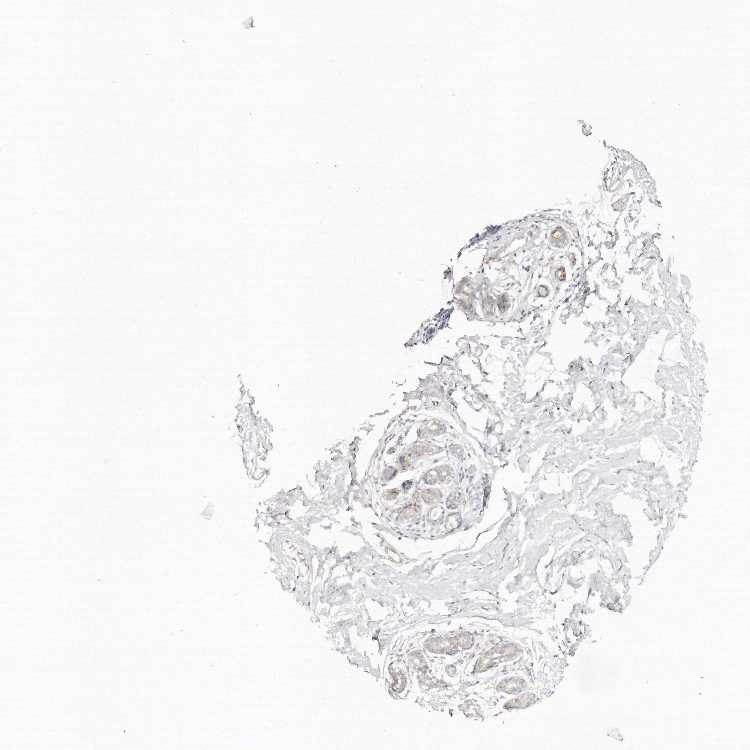

BREAST - Antibody stainingi

Antibody staining in the annotated cell types in the current human tissue is reported as not detected, low, medium, or high, based on conventional immunohistochemistry profiling in selected tissues. This score is based on the combination of the staining intensity and fraction of stained cells.

Each image is clickable and will lead to virtual microscopy that enables deeper exploration of all samples and also displays staining intensity scores, fraction scores and subcellular localization as well as patient and tissue information for each sample.

Antibody HPA027091

Adipocytes Not detected

Glandular cells Low

Myoepithelial cells Not detected